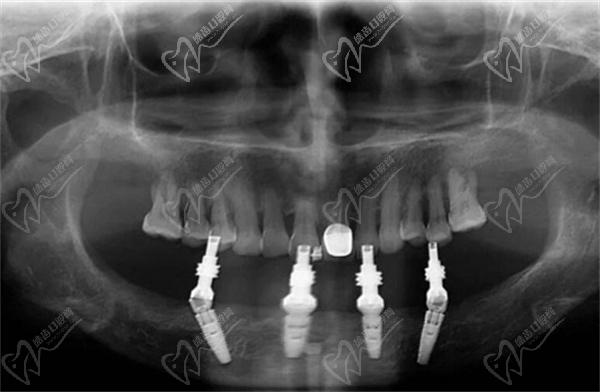

一、all on 4种植牙+马龙桥种植图解

【马龙桥】

【All-on-4种植技术】

马龙桥(Malone Bracket)是由葡萄牙有名口腔种植牙名医 保罗·马龙(Paulo Malo)博士提出和发展的一种修复方案。其主要原理是在缺失牙齿部位安装一个“桥架”,然后将牙冠一个一个的安装上去,注意马龙桥牙的牙冠是独立存在的,如果有一个损坏只更换一个牙冠即可。但是all-on-4种植牙是安装4个植体,然后安装一个连接冠,如果其中一个牙冠损坏,需要更换连接冠。